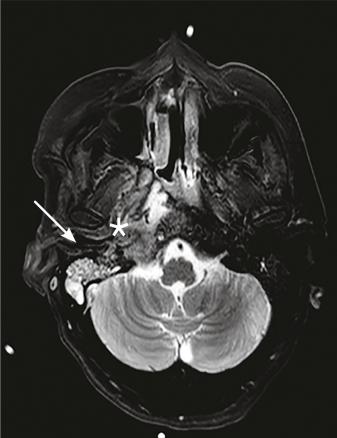

Cette femme de 45 ans était admise aux urgences à la suite d’une hémiplégie gauche. Une imagerie par résonance magnétique (IRM) cérébrale montrait un accident vasculaire cérébral ischémique aigu du territoire de l’artère cérébrale moyenne droite (fig. 1 ) avec occlusion de l’artère carotide droite. Par ailleurs, il y avait un comblant otomastoïdien droit (fig. 2 ) avec collection abcédée parapharyngée homolatérale (fig. 2 ) et thrombose de la veine jugulaire interne droite étendue au sinus sigmoïdien et latéral (fig. 3 ). Après 21 jours d’antibiothérapie intraveineuse combinée à l’anticoagulation, l’IRM de contrôle montrait une recanalisation de la carotide interne et de la veine jugulaire interne.